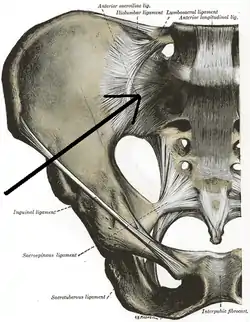

| Anterior sacroiliac ligament | |

The anterior sacroiliac ligament consists of numerous thin bands, which connect the anterior surface of the lateral part of the sacrum to the margin of the auricular surface of the ilium and to the preauricular sulcus.